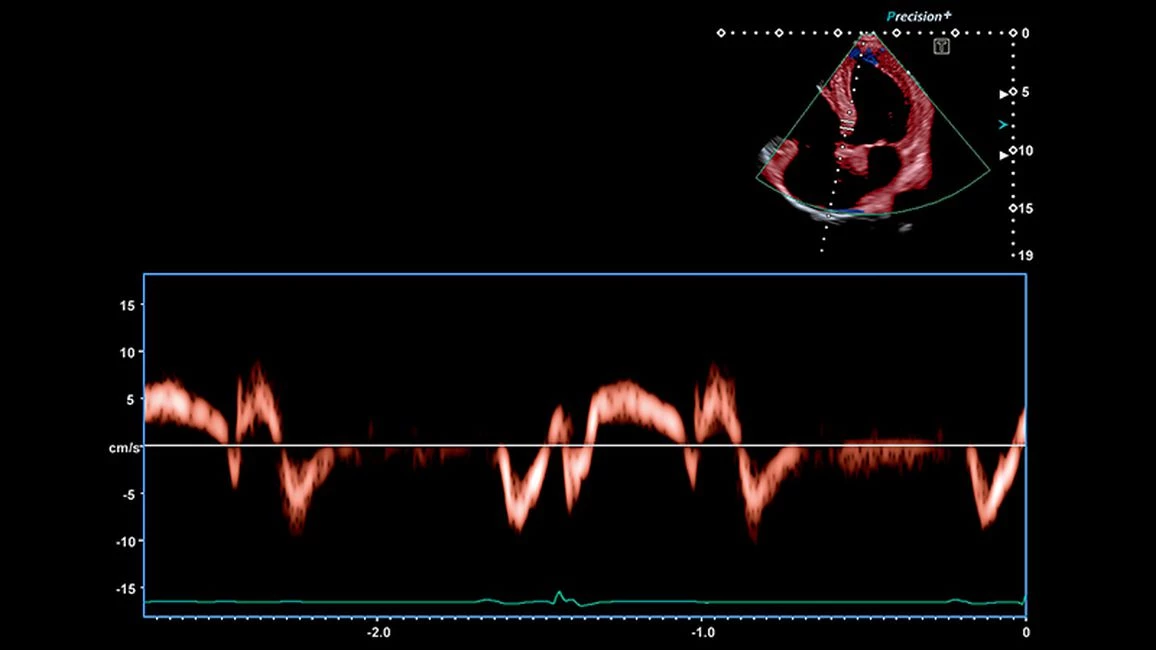

- Quad-Chamber Tracking - отображает кинетику нескольких камер сердца на одном экране в режиме 3D, вместе с параметрическими кривыми

- Тканевой допплер: ✔

Технология Flex-M позволяет получать анатомически правильные срезы в М-режиме в режиме онлайн, а также на основе сохраненных 2D-изображений с тем же качеством, что и в обычном М-режиме. При анатомическом М-режиме можно вращать курсор под произвольным угл